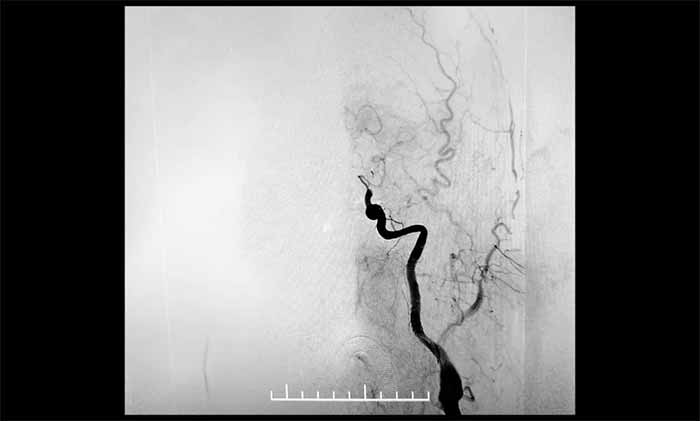

▲ DSA显示,左颈内动脉C7段闭塞

▲ 左颈内动脉顺利开通